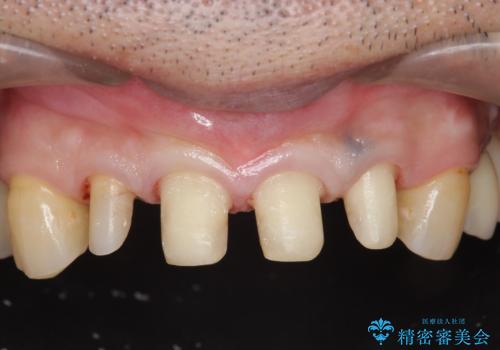

虫歯のマイクロスコープによる丁寧な除去、根管治療、深い虫歯に対する挺出(エクストリュージョン)および歯周外科を行ったのち精度の高いセラミッククラウン製作治療を計画します。

虫歯の放置により、根管治療や深い虫歯に対する処置が必要になりましたが丁寧に一つづつ処置を行ったことで抜歯をすることなく歯を残すことができました。

セラミッククラウンの製作をする前に、歯内・歯周環境の整備は非常に大切です。